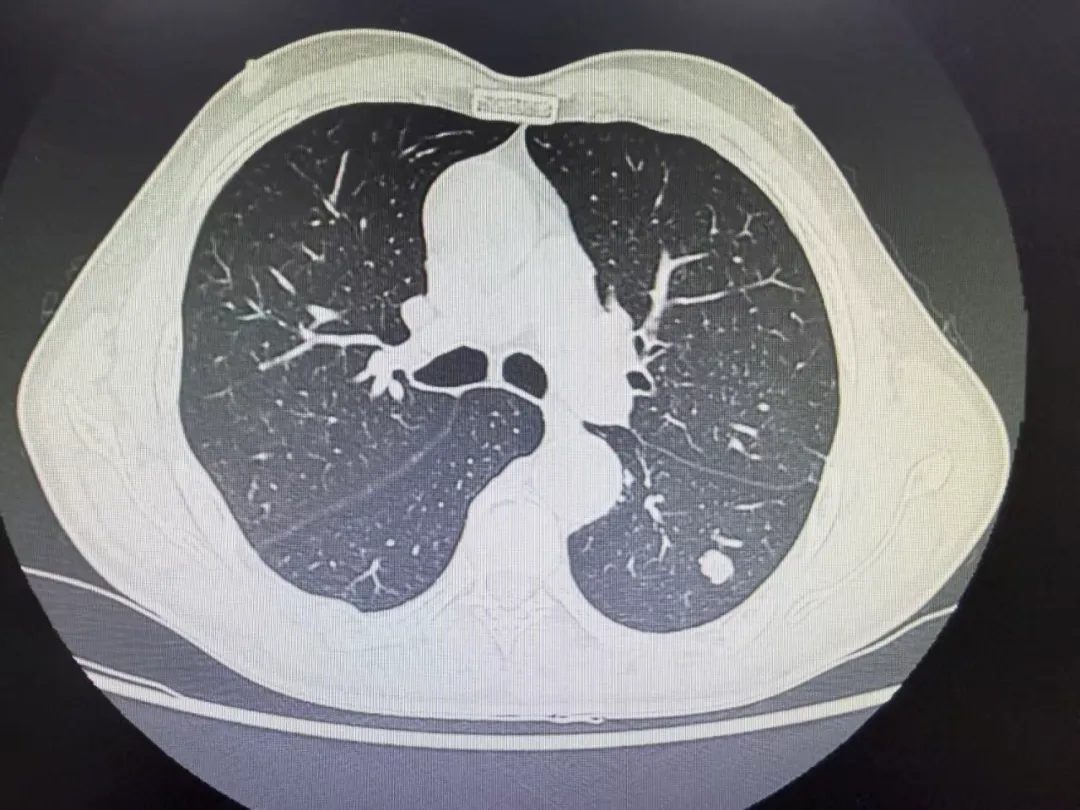

患者公某,于当地医院查体发现左肺下叶肿物,大小约12mm,就诊我院拟行手术治疗,后经张振江主任阅读病史及综合分析后,考虑为良性结节,决定立即中止手术继续随访。后经患者两次随访观察,目前肺肿物大小较前无明显变化。

2025.07.01胸部CT

2026.02.03胸部CT